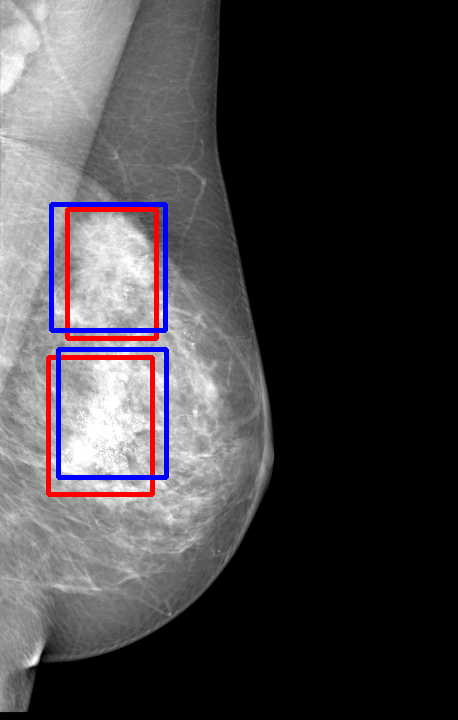

UDA has been extensively studied in case of natural images, utilizing techniques such as adversarial learning [21],pseudo-label training [6, 21, 40], image-to-image translation [40], graph reasoning [20], and adaptive mean Teacher training [6], improving domain adaptation efficiency of object detectors. Recently multiple works focused on using Mask autoencoders (MAE) methods in large-scale pretraining for vision models, involving masking parts of input and reconstructing them [12, 33]. However, these approaches overlook domain shifts. Alternatively, widespread utilization of Teacher-Student models, wherein a Teacher provides pseudo-labels for target domain (unlabeled images) to supervise a Student model, leads to notable adaptation improvements [40, 43]. However, these techniques face the challenge of incorrect predictions and excessive false positives per image due to low-quality pseudo-labels, particularly for medical imaging problems. Pseudo-labels are filtered from the Teacher model’s outputs based on the confidence score threshold. Selecting numerous pseudo-labels with low thresholds leads to inclusion of incorrect predictions, and compromising performance. Conversely, higher thresholds yield a limited number of pseudo-boxes, resulting in sub-optimal supervision. Existing Teacher-Student models often produce pseudo-labels riddled with errors and false positives, as illustrated in Fig. 1(a) and Fig. 1(b). Though [21, 40, 43] utilize techniques like adversarial alignment, weak-strong augmentation, and selective retraining of Student model to minimize the false positives in pseudo-labels, these approaches fail on medical images.

Contributions of this work. We note that screening mammography inherently differs from natural images, with breast abnormalities such as masses, asymmetries, and micro-calcifications, typically much smaller in comparison to the salient objects present in natural images, emphasizing the need for approaches specific to this problem. To address these issues, we make following contributions in this work: (1) We introduce D-MASTER, a transformer-based Domain-invariant Mask Annealed Student Teacher Autoencoder Framework for cross-domain breast cancer detection from mammograms (BCDM), integrating a novel mask-annealing technique and adaptive confidence refinement module. Unlike pretraining with mask autoencoders (MAEs) [12], leveraging massive datasets for training and then fine-tuning on smaller datasets, we present a novel learnable masking technique for the MAE branch that generates masks of different complexities, which are reconstructed by the DefDETR [44] encoder and decoder. Our approach, as a self-supervised task on target images, enables the encoder to acquire domain-invariant features and learn better target representations as shown in Fig. 1(c). (2) In Teacher-Student model, since the pseudo-label noise generated by the Teacher affects the Student model severely, we propose an adaptive confidence refinement module that progressively restricts the confidence metric for pseudo-label filtering. During the initial adaptation phase, soft confidence is applied allowing more pseudo-labels to learn better target representations. Subsequently, as confidence gradually increases, the focus shifts towards enhancing detection accuracy by prioritizing more reliable pseudo-labels. (3) We release a bounding box annotated subset of 1000 mammograms from the RSNA Breast Screening Dataset (referred to as RSNA-BSD1K) to support further research in BCDM. (4) We setup a new state-of-the-art (SOTA) in detection accuracy for UDA settings. We report a sensitivity of 0.74 on INBreast [25] and 0.51 on DDSM [18] at 0.3 FPI, compared to 0.61 and 0.44 using current SOTA respectively. Significant performance gains are also observed on our in-house and RSNA-BSD1K datasets.